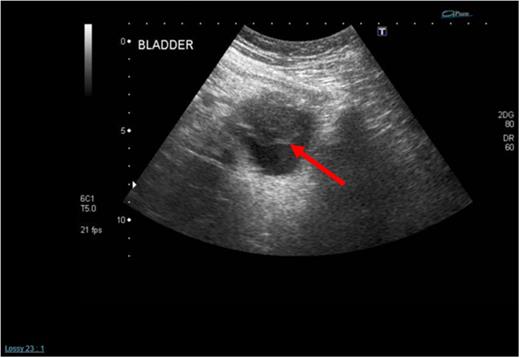

A 62-year-old female presented with a 5-day history of visible haematuria. Clinical examination was unremarkable. Full blood count analysis revealed a haemoglobin of 58 g/L prompting transfusion of 3 units of packed red cells. An ultrasound scan (USS) identified an abnormal soft tissue mass arising from the superior aspect of the urinary bladder with vascular flow within it, raising the suspicion of a malignant neoplasm (Fig. 1).

Initial admission USS of the urinary bladder demonstrating a solid mass within it (see red arrow).